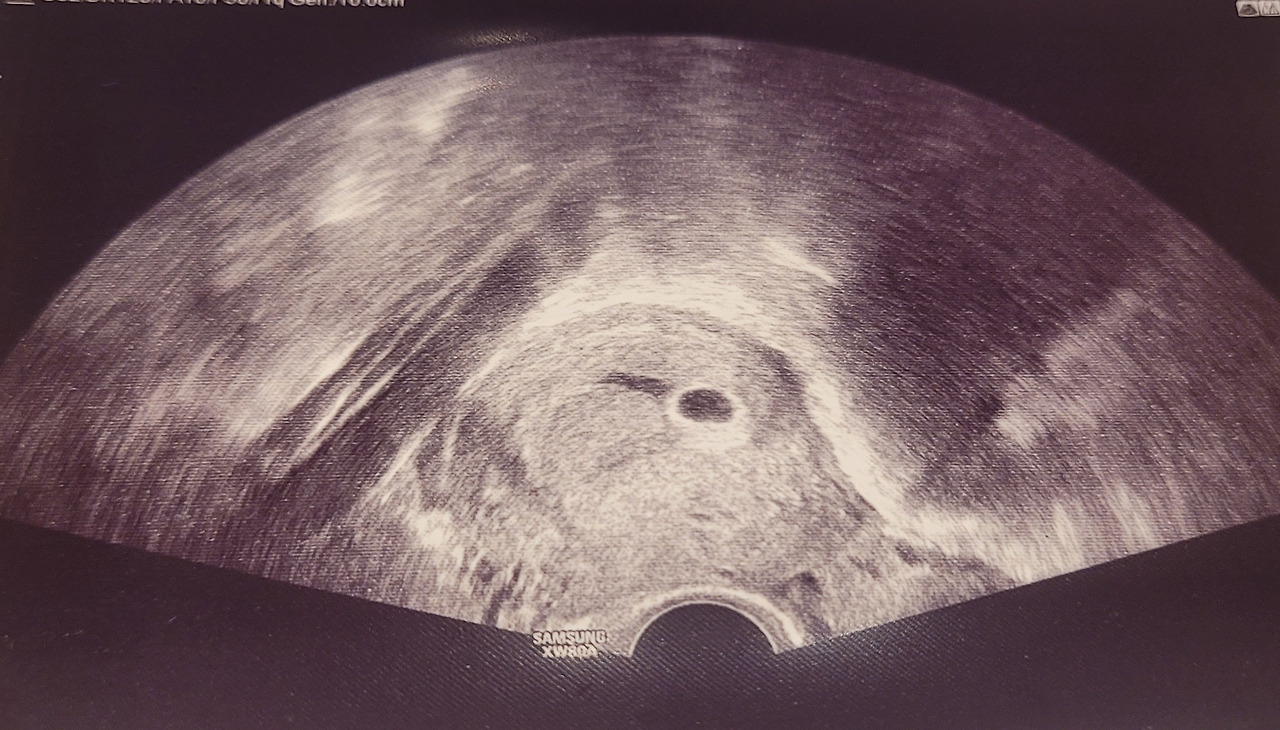

초음파 화면에서 조그마한 게 보인다.

"여기 보시면 아기집이 있고, 특별한 건 없어요."라는 말이 들렸다.

"10주면 배로 초음파를 볼 수 있는 시기니까 배로 볼게요."

의사 선생님께서 배초음파를 보는데 화면에 까만색이 잡혔다.

골반쪽으로 내려왔을 때 화면에 태아가 잡혔다.

"주수에 맞고, 심장소리도 잘 뛰고 있어요."

"자궁경부 길이도 좋아요."